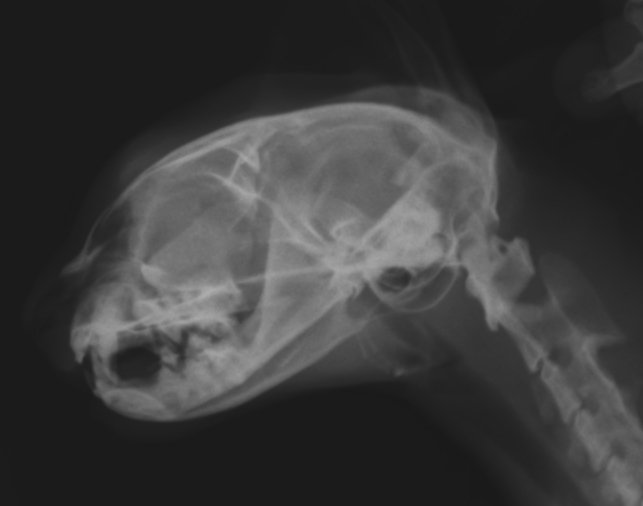

При опухолях, затрагивающих костную ткань ,основным методом диагностики является рентгенографическое исследование, которое покажет размер и характер развития опухоли.Недифференцированные опухоли ротовой полости у собак часто обнаруживаются у крупных пород в возрасте между 6 и 22 месяцами. Они несвойственны молодым особям, но иногда такое тоже может произойти. Один из видов ротовой опухоли — недифференцированная злокачественная опухоль ротовой полости, такая опухоль не может быть распознана простым биопсическим анализом.

При индуктивных одонтогенных опухолях клетки формируют твердые зубные ткани, которые легко можно идентифицировать на рентгеновских снимках.

Остеосаркома полости рта развивается в основном у собак средних и крупных пород и, как правило, в среднем или старшем возрасте. Остеосаркома чаще встречается в нижней челюсти и реже в верхней . Саркому следует дифференцировать от остеомиелита, туберкулеза и кистозной дегенерации кости челюсти.